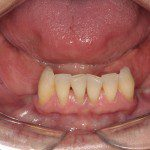

- Antes

- Sorriso inicial